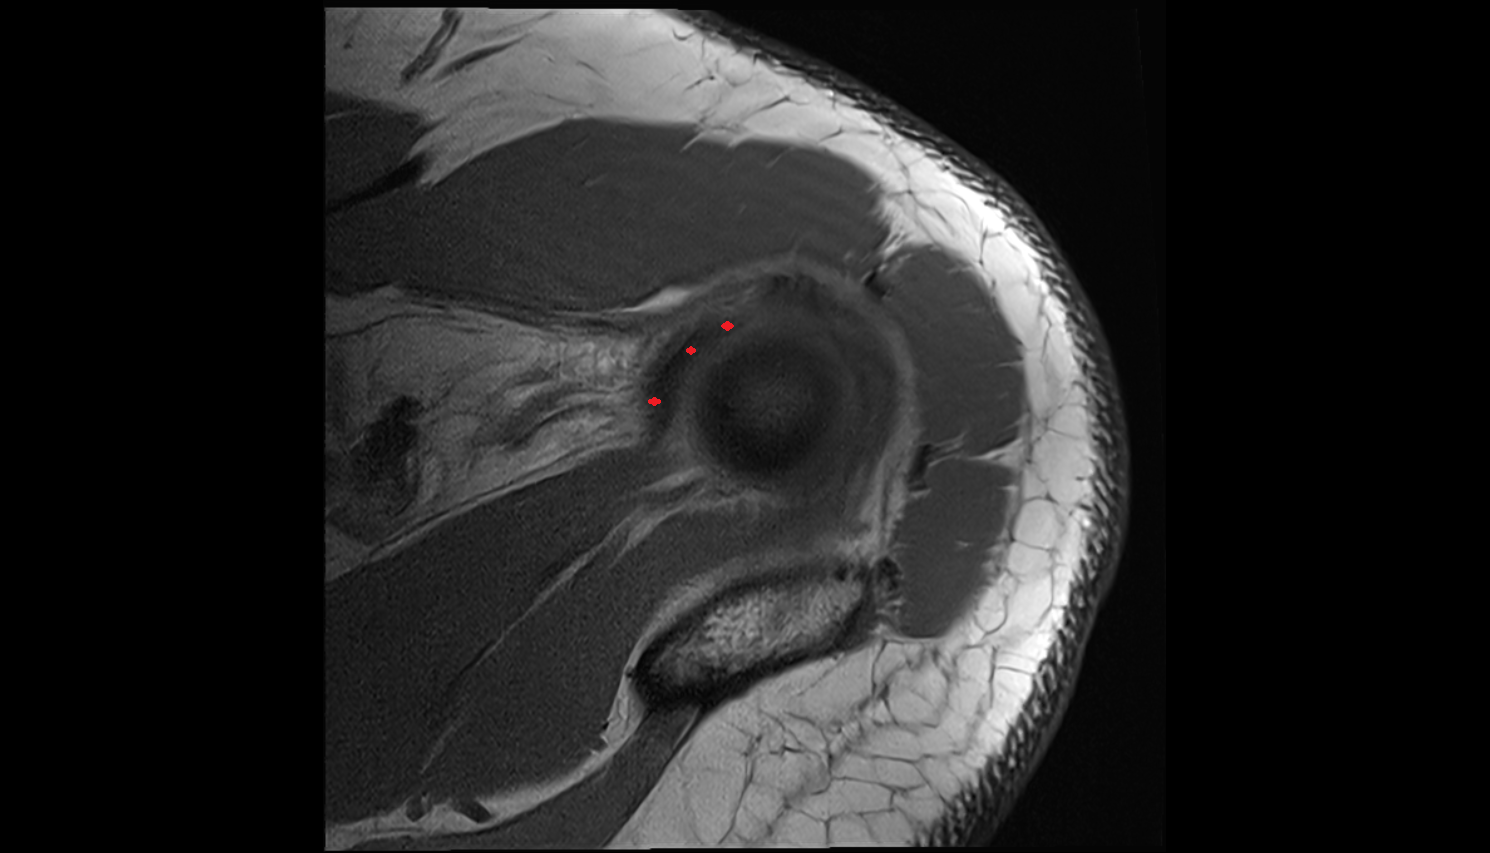

- Glenoid fossa

- Head of humerus

- Glenoid labrum

- Shoulder joint (glenohumeral joint)